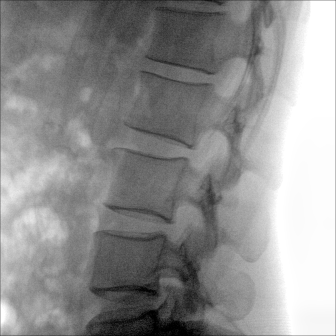

大尺寸動態(tài)平板探測器,高DQE、低噪聲、圖像清晰。采用多分辨率圖像增強處理技術(shù),不同部位不同圖像處理算法,滿足客戶多樣化的需求。

多角度自由旋轉(zhuǎn),滿足患者復(fù)雜擺位需求。